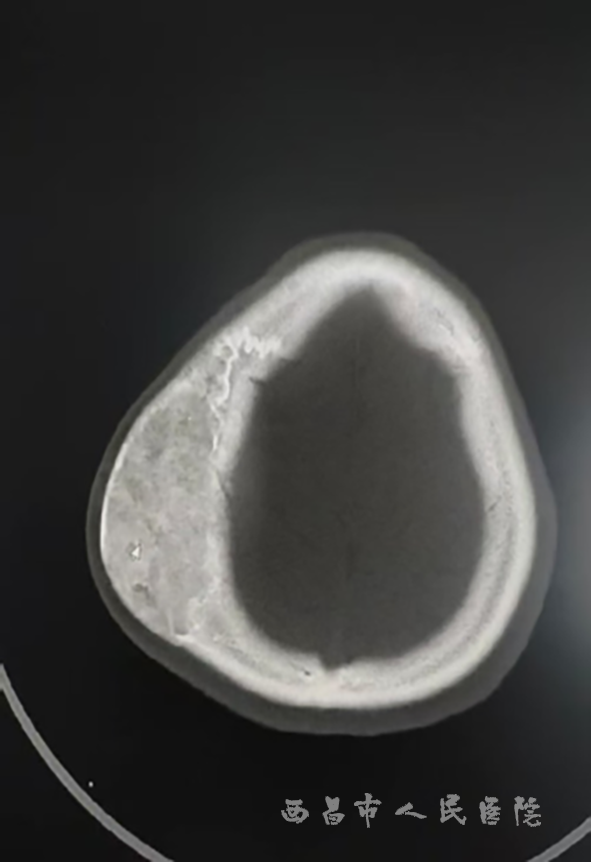

机化后的血肿

答:头皮血肿一般不需要特异性治疗,早期给予冷敷以减少出血、减轻疼痛,多数在数日或数周内自行消退,消退前注意不要弄破了血肿,以免继发感染。注意每天观察患儿头皮血肿消退的速度,因为血肿的吸收可导致患儿出现高胆红素血症,此时黄疸发生早且重。因此应密切随访患儿皮肤颜色及胆红素情况。当血肿较大时,及时检测血红蛋白及凝血功能,以防失血过多而贫血。定时到神经外科门诊随诊,早期及时处理,均可得到良好恢复。极少数血肿后期可能会出现机化或钙化,必须警惕,一旦头皮血肿长时间无法吸收,逐渐变硬,甚至出现继发感染、骨化、颅骨破坏等,必须至神经外科就诊进行手术治疗。